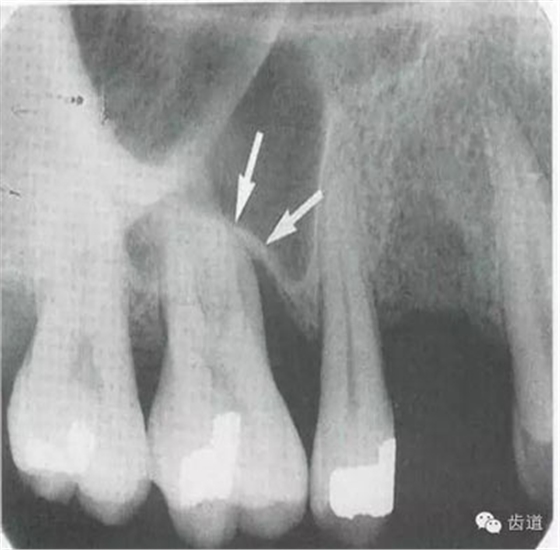

3)頦孔:

位于前磨牙根尖區(qū)域,為一大致圓形密度低的影像。頦孔位置變異大,多位于第二前磨牙根尖稍下,注意與根尖周病變區(qū)別,其要點(diǎn)是牙周膜及其骨硬板是否連續(xù)不斷。

4)外斜線:

由升支前緣下部斜向前下方,為一密度高的帶狀影像。常重疊在第二、三磨牙牙冠處、頸部或根部,使牙髓室或根管不能清晰顯示